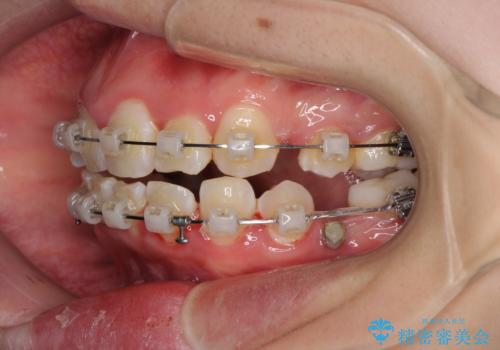

治療中に舌の突出癖が改善されず、下顎前歯が著しく前方に突出して反対咬合となってしまう局面がありました。

アンカースクリューを使用しながら舌癖の改善を図り、何とか咬み合わせを改善することができました。